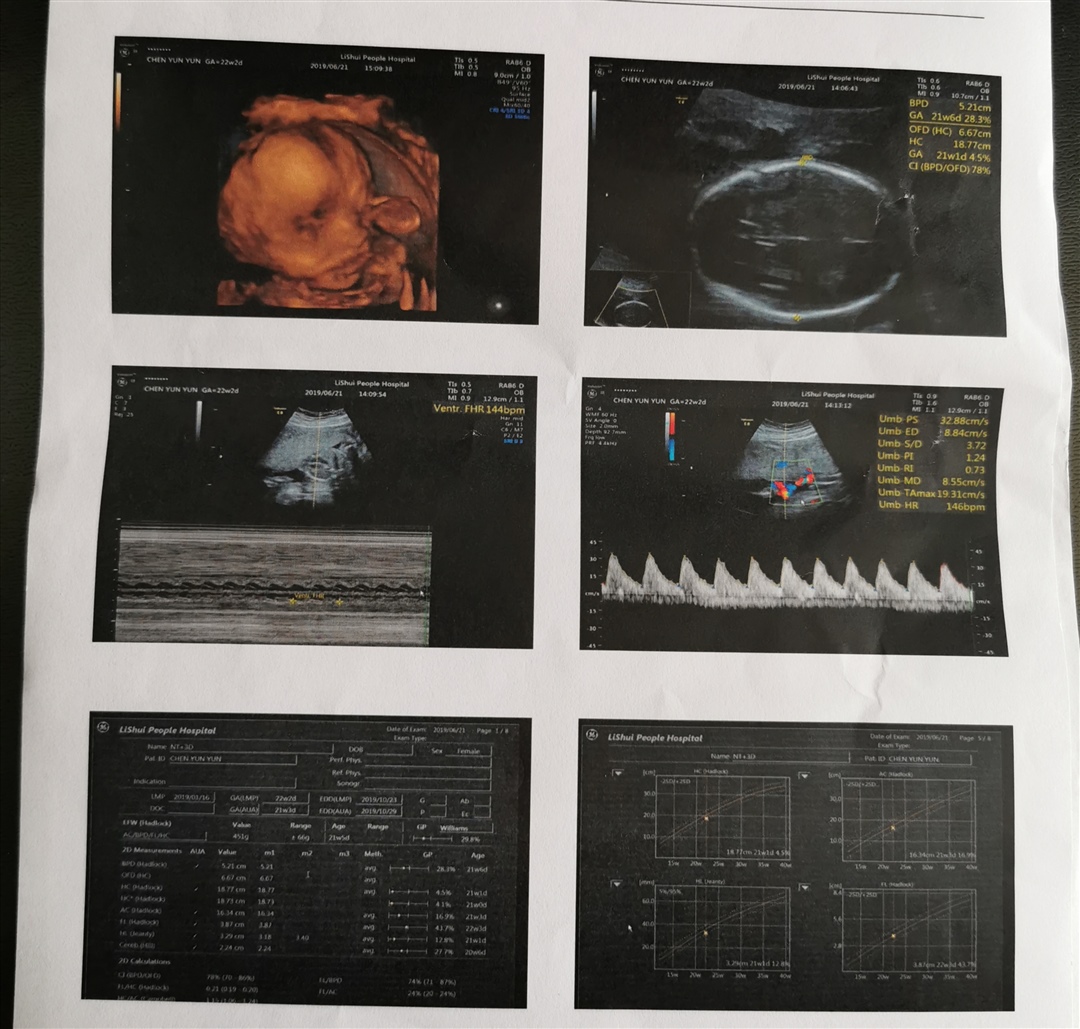

云朵[帖主]:嗯,应该是的,B超检查是女孩